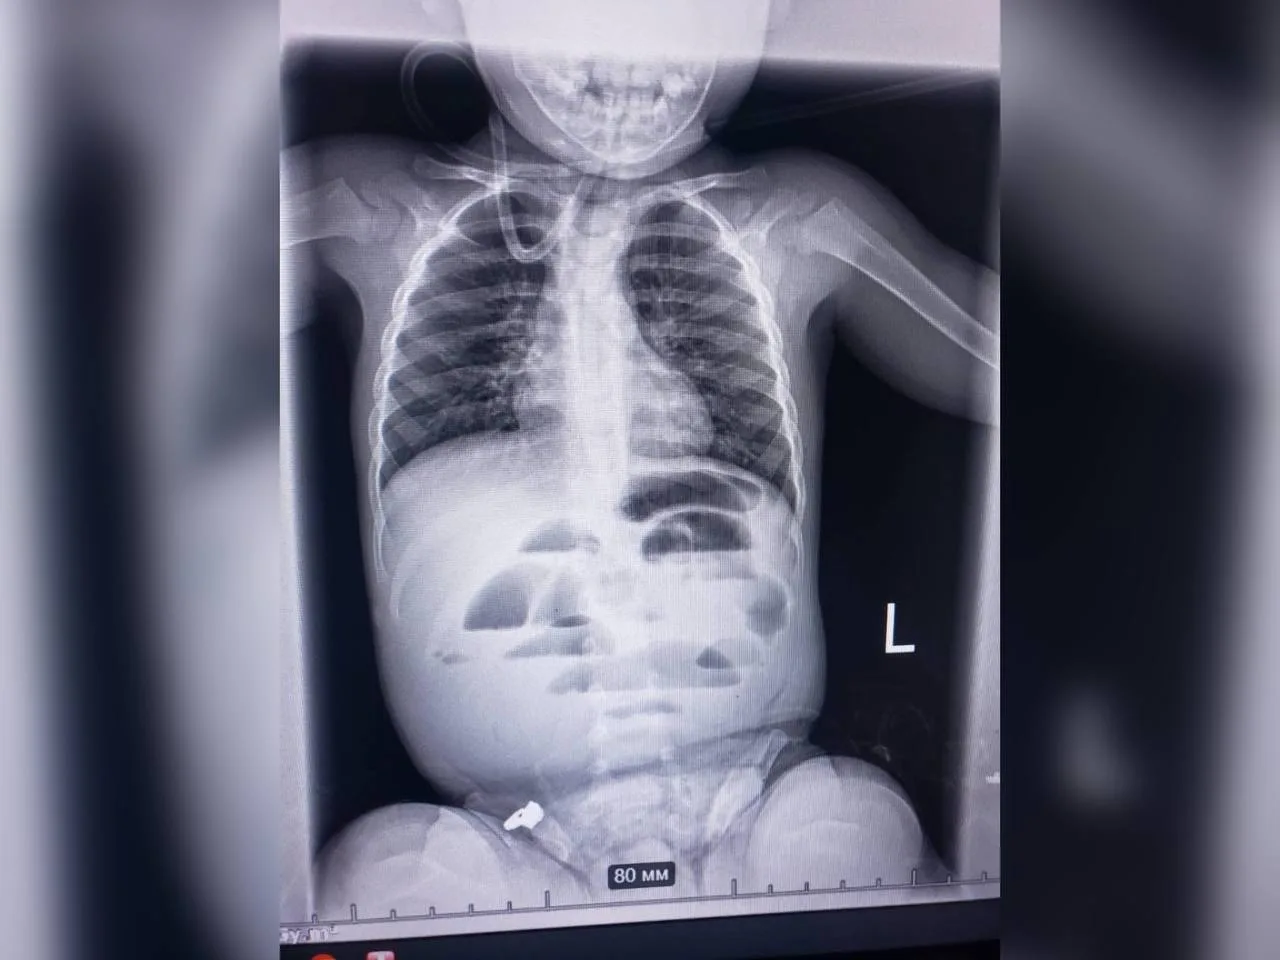

Малюка доставили до регіонального медичного центру родинного здоров’я з підозрою на кишкову непрохідність. Під час рентгенографії виявили ознаки перекриття кишечника, тому лікарі вирішили провести термінову операцію.

Під час втручання виявили стороннє тіло — гідрогелеву кульку діаметром близько 3 см, яка повністю перекривала просвіт кишечника. Її видалили, після чого дитину перевели до відділення інтенсивної терапії.